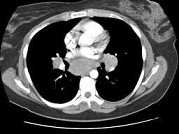

单项选择题女,33岁, 咳嗽,无发热, 结合图像,最可能的诊断是 ( )

A、肺结节病

B、淋巴瘤

C、中央型肺癌

D、胸腺瘤

E、支气管囊肿